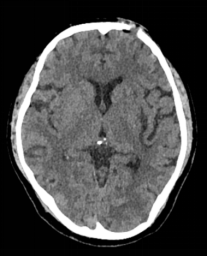

配合早期床边康复治疗,患者恢复理想,住院11天后顺利出院。出院时患者可正常言语交流,右侧肢体肌力恢复至3-4级,可独立步行。出院一个月后患者复查CT显示恢复良好。

患者术后一个月门诊复查头颅CT